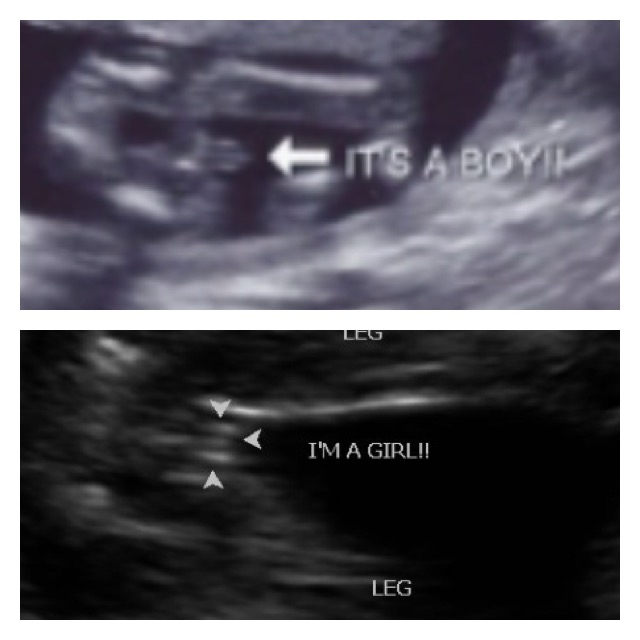

Moim zdaniem Dziewczynka :) Zapamiętałam że przy chłopcu są 3 kreski a.przy dziewczynce 2, dlatego jak w drugiej ciąży usłyszałam, że dziewczynka to byłam zdziwiona bo widziałam trzecią kreskę od razu ;)

Wiesz co 3 kreseczki mogą byc zarówno u dziecwyznki jak i u chłopca tak czytalam.

Tylko zależy duzo czy malo wystaja poza kości udowe :-) bo córka pamiętam ze tez miala 3 kreseczki